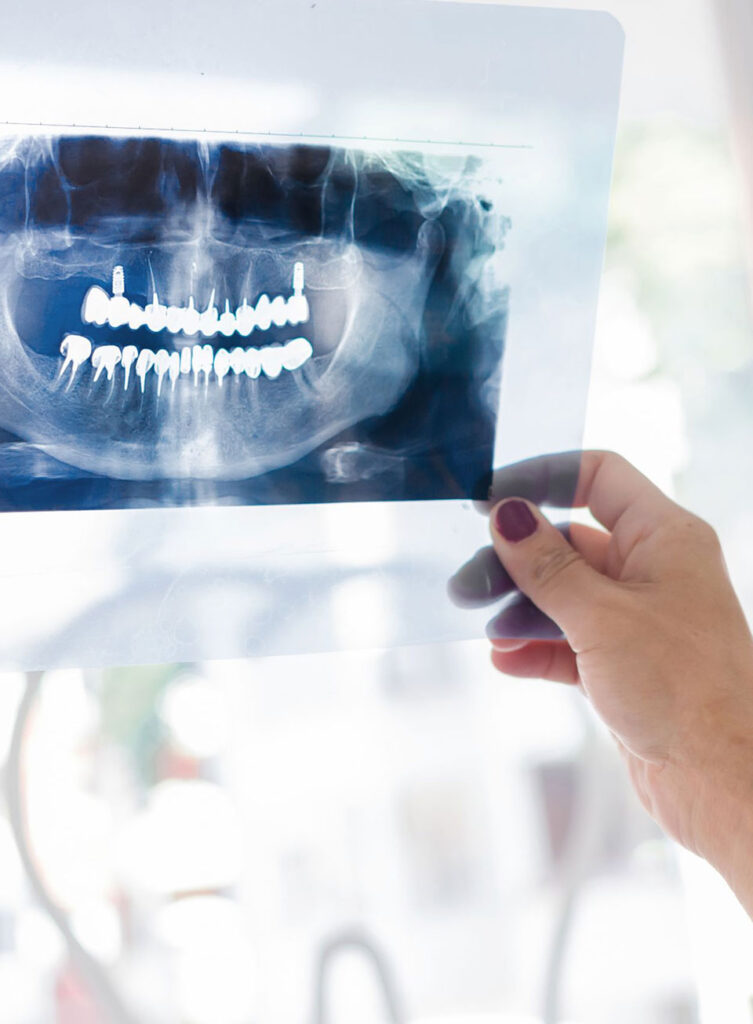

Nel nostro studio è presente una sala radiologica con un modernissimo sistema di radiologia digitale a basse dosi radiogene che permette in breve tempo di ottenere immagini nitide e chiare.

La radiologia odontoiatrica risulta spesso indispensabile per ottenere tutti gli elementi diagnostici necessari a stilare ed eseguire un corretto piano di cura.

I sistemi di “imaging” e diagnostica per immagini radiologiche sono utilizzati ad esempio in caso di: carie, fratture, cisti, parodontiti, devitalizzazioni, estrazioni, estrazioni dei denti del giudizio, ortodonzia, riabilitazioni implantari.

Nel nostro studio è presente una sala radiologica con un modernissimo sistema di radiologia digitale a basse dosi radiogene che permette in breve tempo di ottenere immagini nitide e chiare:

– Rx endorali (specifiche per ogni singole dente);

– OPT(ortopantomografia) ;

– Telecranio in proiezione latero-laterale/postero-anteriore

– Radiologia della mano per la valutazione dello stato di crescita

– TAC dentale 3D cone beam (CBCT).

Tali immagini possono così esser utilizzate per l’analisi e progettazione del caso tramite potenti software 3D.